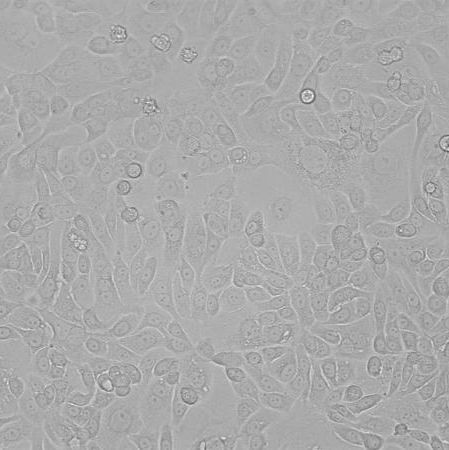

OVKATE_人卵巢癌细胞

细胞名称: OVKATE_人卵巢癌细胞

种属来源: 人

性别年龄: 女性,40岁

种属来源: 卵巢

生长特性: 贴壁生长

细胞形态: 上皮细胞样

培养条件: RPMI1640 +10% fetal bovine serum,37 ℃, 5% CO2

细胞规格: 1 X 106cells/T25或1 mL冻存管

传代方法:1:3传代, 2-3天传1代

冻存条件: 90% FBS + 10% DMSO